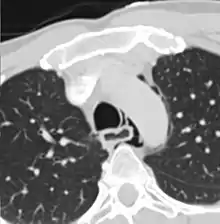

Axial CT image through the upper chest showing extraluminal air (Pneumomediastinum) surrounding the trachea and esophagus

The diagnosis of Boerhaave's syndrome is suggested on the plain chest radiography and confirmed by chest CT scan. The initial plain chest radiograph is almost always abnormal in patients with Boerhaave's syndrome and usually reveals mediastinal or free peritoneal air as the initial radiologic manifestation. With cervical esophageal perforations, plain films of the neck show air in the soft tissues of the prevertebral space.

Hours to days later, pleural effusion(s) with or without pneumothorax, widened mediastinum, and subcutaneous emphysema is typically seen. CT scan may show esophageal wall edema and thickening, extraesophageal air, periesophageal fluid with or without gas bubbles, mediastinal widening, and air and fluid in the pleural spaces, retroperitoneum or lesser sac.